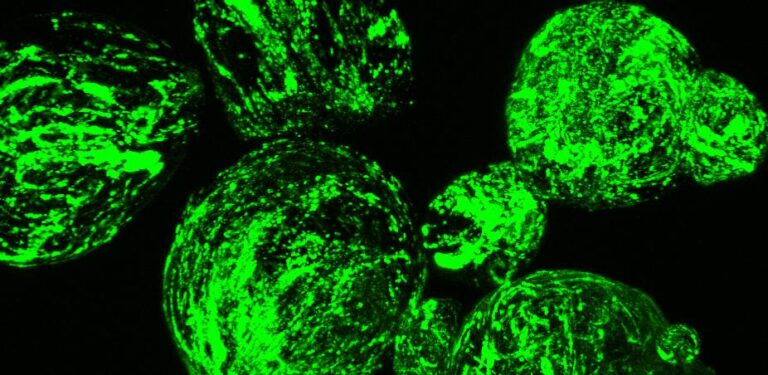

The tiny robots – just micrometers across – are being developed by Professor František Štĕpánek and colleagues at the Chemical Robotics Laboratory at the Institute of Chemical Technology in Prague, Czech Republic. The idea is that these smart structures, which resemble single-celled organisms, swarm where they are needed – at a tumour site or industrial spill, and release chemicals when triggered.Prof. Štĕpánek, who had previously worked in the pharmaceutical industry, realised that a lot of potentially useful molecules were simply not stable enough for industry to make easily and package into pills.So he shrank the lab. The tiny robots, called ‘chobots’, are designed to act as mini drug factories – mixing component chemicals and synthesising short-lived drugs where and when they are needed, and on command.‘They are entities similar in structure and size to single-celled organisms like bacteria, but they are not living,’ said Prof. Štĕpánek, who moved from Imperial College in London back to the Czech Republic afterreceiving a European Research Council grantfor the CHOBOTIX project. ‘And they can only do something when given a command, like a machine.’He is now working as part of the EU-funded MICREAgents project, which brings together researchers from Germany, Denmark, Italy, the Czech Republic, the Netherlands, Israel, and New Zealand to make microscopic electronically active agents for chemical information processing.Professor František Štĕpánek, Institute of Chemical Technology in Prague, Czech Republic.Professor František Štĕpánek, Institute of Chemical Technology in Prague, Czech Republic.Prof. Štĕpánek said his chobots could, for example, be triggered by a magnetic nanoparticle attached to the robot cell. In this case, applying a radiofrequency field for a short period of a few minutes would increase the temperature of the robots but nothing else, so that if the chobots were in body tissues these would be unaffected. This field would raise the temperature such that storage reservoirs inside the chobot would melt, releasing their contents and so allowing the synthesis of the target drug.‘The nice fact is that the opening of the reservoirs is a reversible process,’ said Prof. Štĕpánek. ‘It’s possible to open and close them repeatedly.’ The potential of this is that the researchers could control a sequence of doses over time.But how do the chobots know where to go? The team has been looking at tagging their surfaces with specific markers to drive them to the desired location. In the human body, this is by attaching antibodies to them which can recognise cancer cells. Tumour cells, for example, have many known markers which they carry on their surfaces, so it is possible to engineer the chobots to carry antibodies which will home in on, and only stick to tumour cells.Prof. Štĕpánek’s team showed ina study published online in Octoberthat by using an antibody called M75, they could get their artificial cells to specifically attach to markers associated with common cancer cells.The concept of using tiny vehicles for drug delivery in this way is not new. But synthesising drugs on location sets this project apart from previous work, Prof. Štĕpánek said.Another clinical use could be to help beat antibiotic resistance in patients, Prof. Štĕpánek said, because the drugs they can manufacture are short-lived. ‘If they are released to where the bacteria are present, they will either kill them, or they don’t. But they are unstable so they don’t stay in the environment long enough for bacteria to evolve (resistance),’ he explained.They might also be used for agrochemicals to fight against plant pests and fungi; and even in perfumery to produce short-lived molecules which give the ephemeral scents of freshly cut flowers or sliced cucumber, he said.Swarm roboticsIn all of these potential applications, the chobots will harness the strength of numbers, in what is known as ‘swarm robotics’. Inspired by nature – the swarming of ants and bees – relatively complex tasks can be carried out by the simple actions of thousands of individuals. The quantity of chemicals each chemical robot could release is negligible, said Prof. Štĕpánek. By luring large numbers to the same location and triggering them at the same time, they can have a significant co-ordinated effect.“‘They are entities similar in structure and size to single-celled organisms like bacteria.’Professor František Štĕpánek, the Institute of Chemical Technology in Prague, Czech RepublicSo far, Prof. Štĕpánek’s team have studied their chobots in cell cultures, but he hopes they will move on to animal safety studies in the next year. And if all goes well, they may be looking at the first human safety studies in 2015 or 2016.The project is ‘exciting’ said Dr Omid Farokhzad, associate professor at Harvard Medical School and director of the laboratory of nanomedicine and biomaterials at Brigham and Women’s Hospital in Boston, US. He looks forward to seeing the team demonstrate the effectiveness of their approach in validated animal models. Dr Farokhzad predicts that in the next 10 or 20 years ‘smart therapeutics’ like this, which harness nano- or micro-particles, will be seen in the clinic.The biggest challenge to developing these artificial cells, Prof. Štĕpánek said, is making sure they are safe in humans and do not trigger an immune response. To help overcome this, the team uses biocompatible materials to build the chobots, for example by using materials already known to be accepted by the human body like food additives or lipids.Another challenge in the future may be the cost of scaling up the manufacture of these complex, artificial cells.